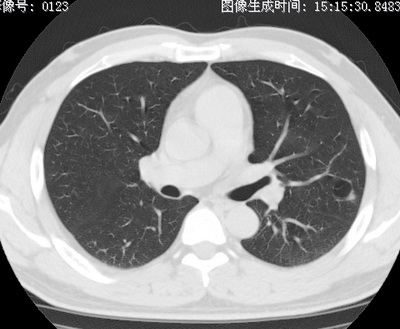

以下是引用zhao_bin2008在2010-1-4 20:15:00的发言:[br]先天性肺囊肿或小的肺隔离症?

以下是引用卜一在2010-1-4 22:09:00的发言:[br]先天性肺囊肿或小的肺隔离症?支持!

以下是引用zsl6918在2010-1-5 5:23:00的发言:[br]良性改变!肺囊肿,先天性支气管闭锁,血管畸形等均有可能。

以下是引用影像之路在2010-1-6 11:10:00的发言:[br]腺癌,最终的病检有些出乎意料之外,术前同志们大多考虑为肺囊肿或小的肺隔离征 [br]回过头来看 小结节呈分叶状,其内侧有一条较粗的静脉供血或许能成为支持诊断腺癌的理由